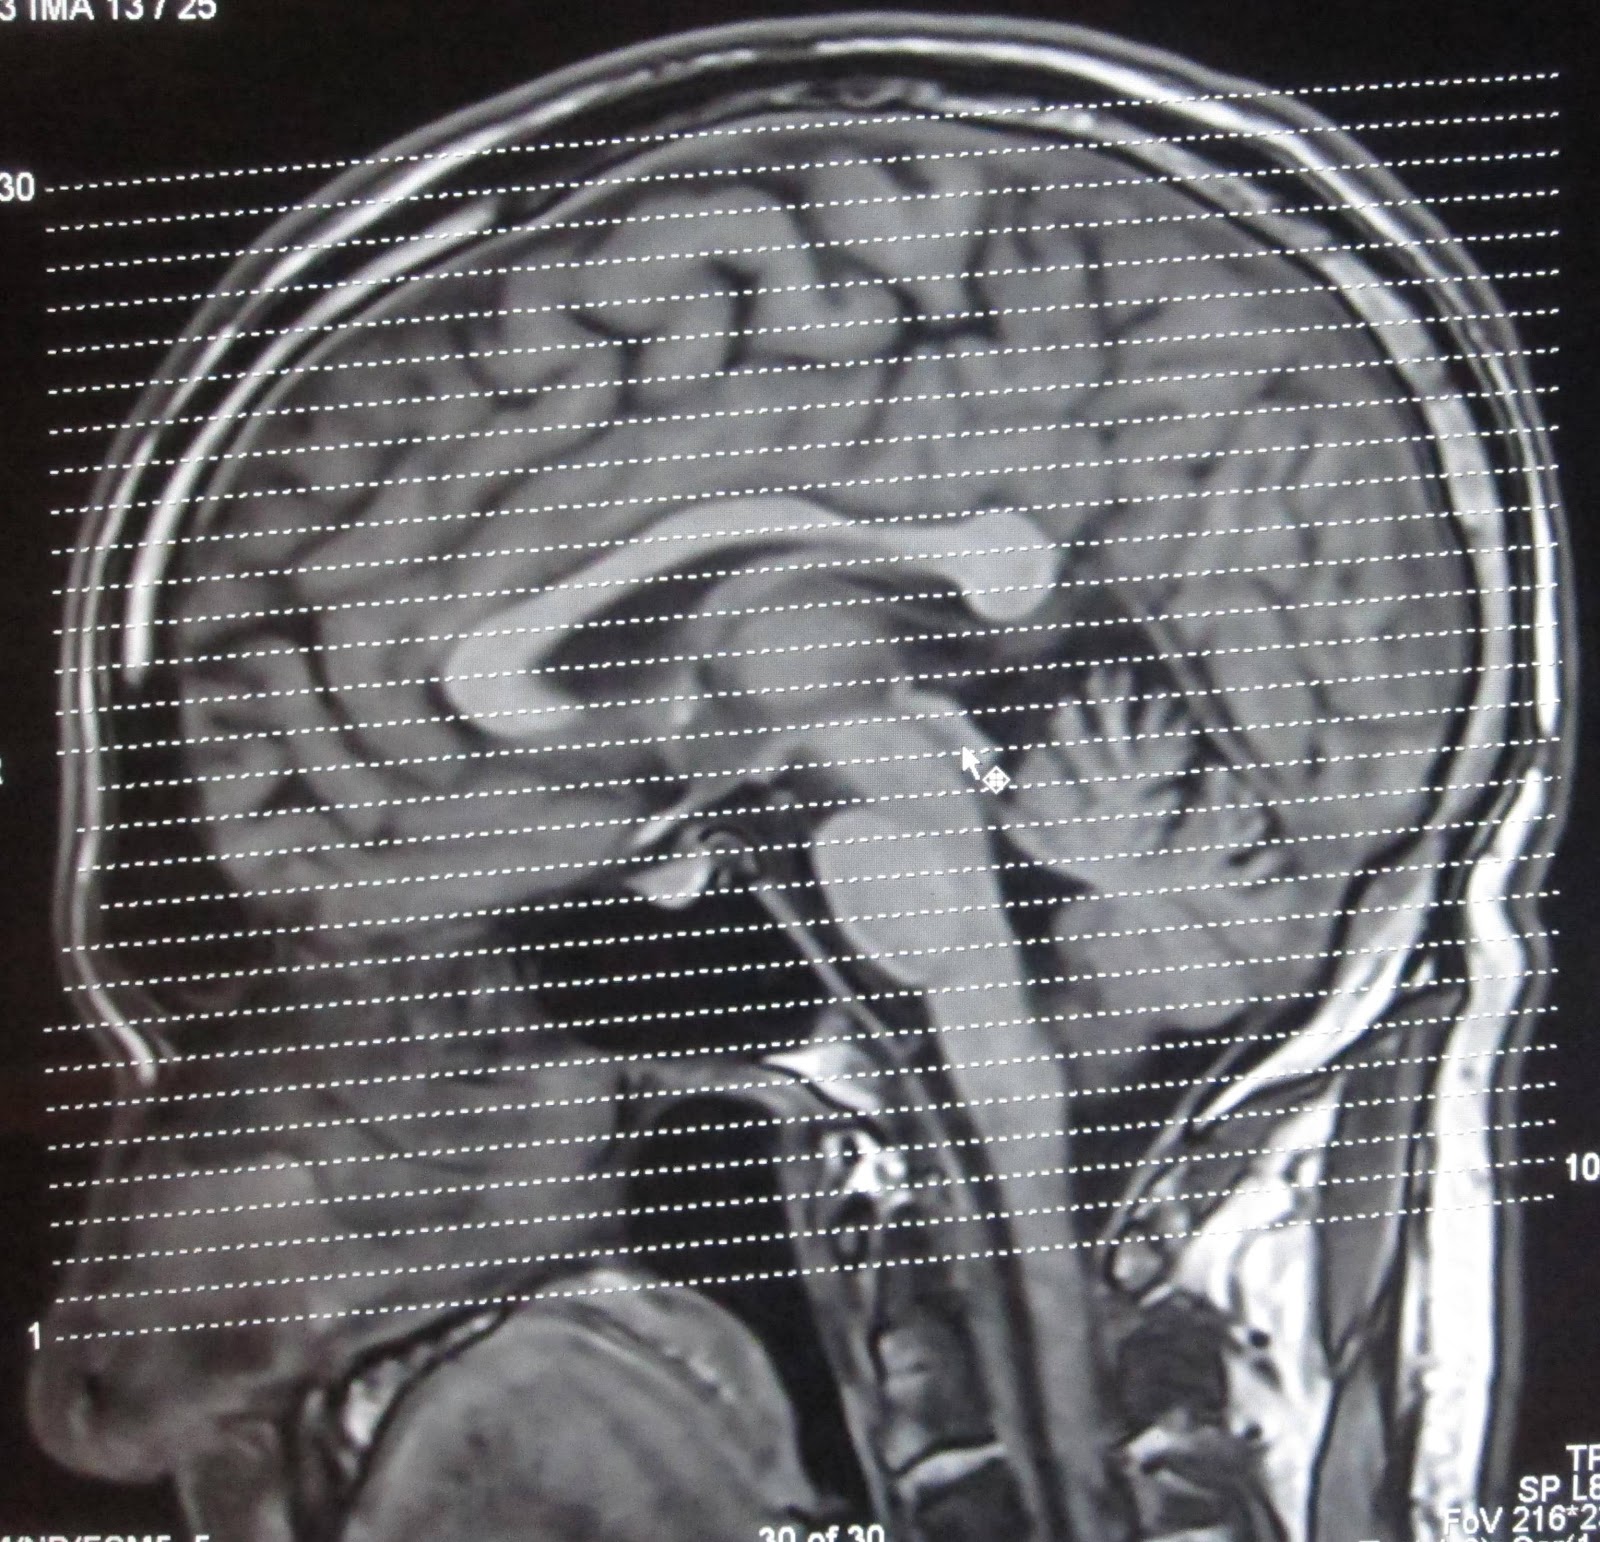

.plane and (c) coronal plane. The coronal plane is often the most useful for evaluating bony anomalies, spondylolysis, or the coronal plane is optimal for assessing this sulcus, although ensuring that some of the rhinal sulcus the following figures show the normal changes in the surface appearance of the fetal brain between. And mapping of vasculature, as well as.

Aka frontal plane, a coronal plane divides the brain into an anterior and posterior portion.